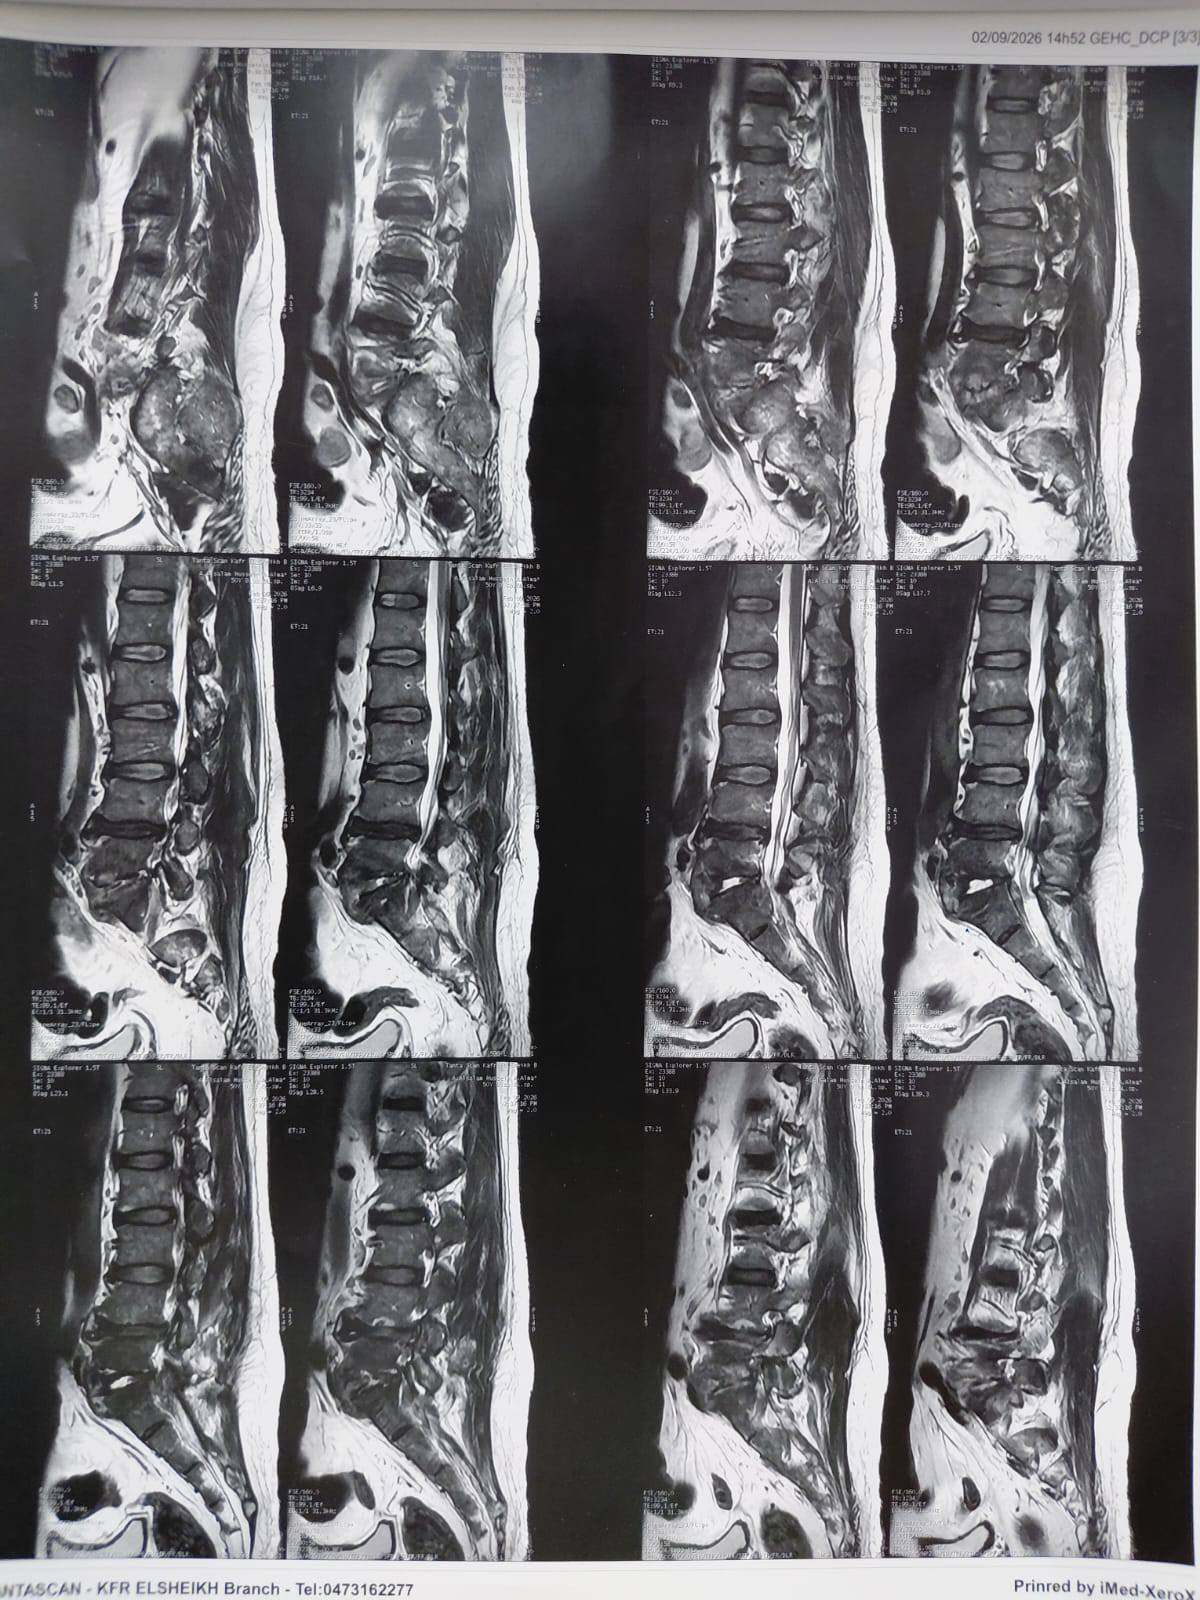

،أ.د/ جمال شمس مدير المستشفى الجامعي الرئيسي،أ.د/ حسام الدين جاد رئيس قسم جراحة العظام نجح فريق قسم جراحة العظام والكسور في إجراء عملية معقدة لالتهاب صديدي بالفقرات مسبب تآكل بالفقرات وضاغط على جذور الاعصاب الطرفية ومسبب ضعف بعضلات الطرفين السفليين مع التأثير على كافة جوانب الحياة للمريض .وقد تمكن الفريق من إزالة الالتهاب والصديد وتثبيت الفقرات وقسم جراحة العظام على أتم استعداد لاستقبال مثل هذه الحالات .